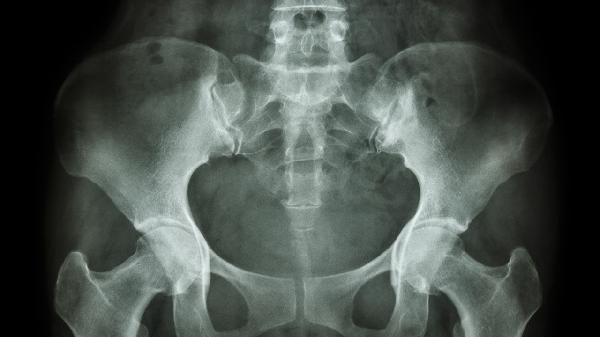

骨盆前倾可能对儿童发育造成体态异常、运动功能受限、脊柱侧弯风险、生长发育迟缓、内脏器官压迫等影响。

骨盆前倾改变身体重心分布,可能影响下肢骨骼受力。儿童正处于骨量积累关键期,异常力学负荷可能干扰髋关节发育,严重时可能导致髋臼发育不良或股骨头缺血性坏死。